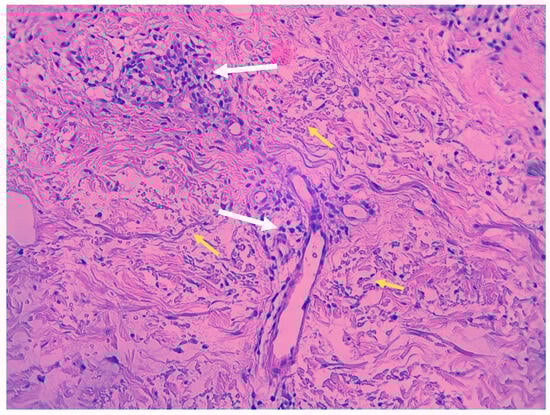

1.2. Histopathology